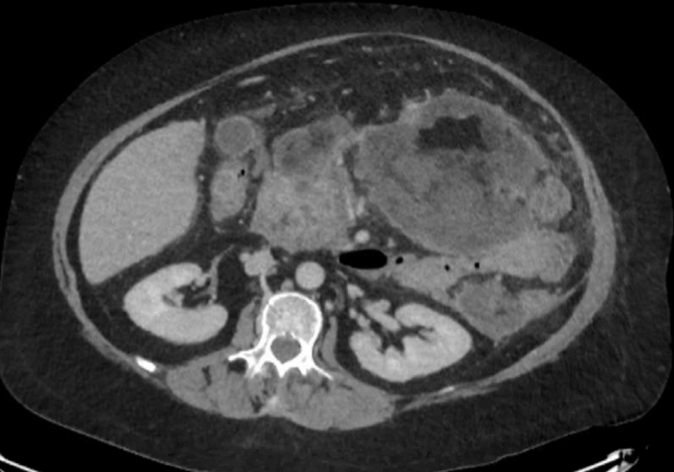

Post-ERCP acute infected necrotising pancreatitis in a patient with Cushing’s disease